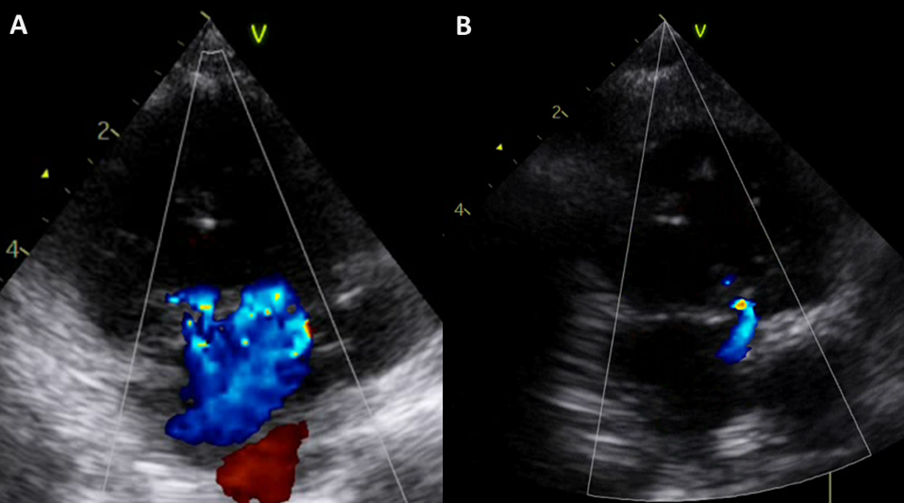

Fig. 2 Image of echocardiography

(A) Image of echocardiography before Fontan procedure. Moderate common atrioventricular valve regurgitation was observed. (B) Image of echocardiography after Fontan procedure pulmonary vein stenosis repair and common atrioventricular valve plasty. Common atrioventricular valve regurgitation was improved.

その後は共通房室弁閉鎖不全の増悪なく成長発達が得られた.2歳2か月時にFontan手術前評価として心臓カテーテル検査などの精査を行った.心臓カテーテル検査は両側の平均肺動脈圧は8,平均下大静脈圧は5,右室容積は109% of normal, RVEFは59%,PA indexは251であった(Table 1).上大静脈造影で右肺動脈への順行性血流を認め,体肺側副血管の発達は左右差を認めなかった.造影CT検査で右下肺静脈狭窄を(Fig. 1B),心エコー検査では共通房室弁閉鎖不全を認めた(Fig. 2A).

術後経過は良好で術後26日の心臓超音波検査では右下肺静脈の径は3.6 mm(Fig. 3)で,房室弁閉鎖不全は改善した(Fig. 2B).術後28日の胸部レントゲンで右肺うっ血なくCTR 41%であった.術後35日に退院した.